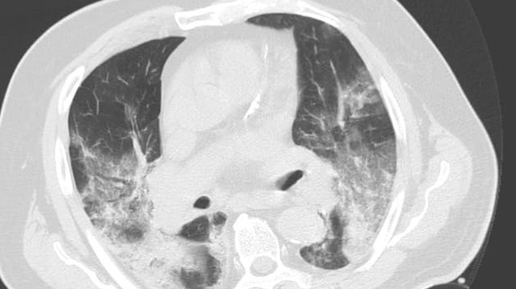

Пневмония является серьезным инфекционно-вирусным заболеванием, которое поражает легкие. Вирусная пневмония является одним из типичных осложнений для коронавирусной инфекции 2019-nCoV (COVID-19). Поскольку некоторые виды вирусной пневмонии проходят бессимптомно, для выявления воспаления легких широко применяют визуализационные методы диагностики. Как правило, пневмонию замечают во время рентгена (нужно сделать боковую и прямую проекцию легких). Однако в некоторых случаях для подтверждения диагноза требуется прохождение компьютерной томографии легких...

КТ повреждает легкие при пневмонии от covid-19

Компьютерная томография (КТ) грудной клетки при диагностике поражения легких от коронавирусной инфекции увеличивает риски развития осложнений пневмонии и рака. КТ дает возможность неинвазивным методом обследовать болезни и получать изображения внутренних органов с помощью рентгеновского излучения...